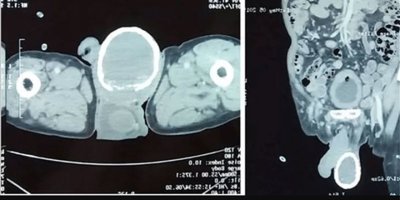

LEFKOŞA DEVLET HASTANESİ’NDE BİR YAPAY KALP AMELİYATINA DAHA İMZA ATILDI TABİPLER BİRLİĞİ: PROSTAT KANSERİ TEDAVİSİNDE EN BELİRLEYİCİ FAKTÖR ERKEN TANI